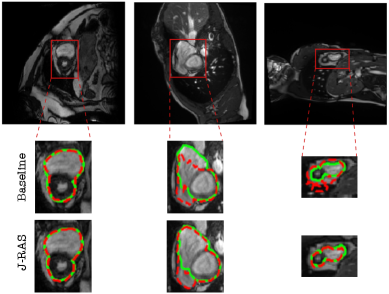

In this section, we qualitatively evaluate the effectiveness of the proposed J-RAS method by comparing its

Refer to caption

segmentation outputs against the baseline SegFormer model. Representative examples from the ACDC test set are presented in Figures (6, 7, 8, 9), with results shown at Top-k=2k=2.

Boundary Precision. Figure 6 highlights boundary precision by presenting representative input slices with ground-truth contours (green) and predicted contours (red). Compared to the baseline, J-RAS achieves tighter alignment with the ground truth, reducing misalignments and producing smoother, more reliable contours. The improvements are particularly evident in challenging cases with anatomical variability or weak contrast, where baseline predictions often fail to capture the true structure. To further illustrate these gains, Figure 7 presents zoomed-in regions of interest, comparing SegFormer alone with SegFormer integrated within J-RAS. This view reveals finer details of the boundaries, showing that J-RAS consistently reduces boundary errors and better adheres to the true anatomy across different views. Even in cases where the baseline performs reasonably well, J-RAS enhances boundary fidelity and strengthens alignment with the ground truth, contributing to improved Dice scores.

Figure 7: Comparison of segmentation results on samples from the ACDC test set. The top row shows the input images with the region of interest highlighted. For each case, the baseline segmentation (middle row) and the proposed J-RAS method (bottom row) are overlaid in comparison with ground-truth annotations (green). Red dashed lines denote model predictions.